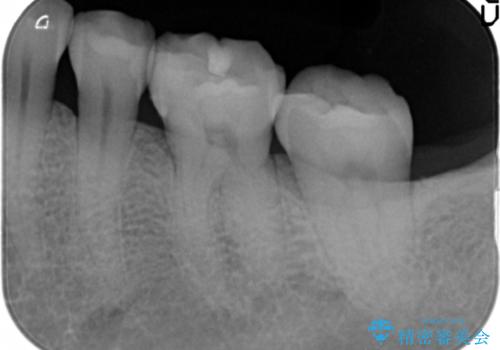

- 銀の詰め物が気になるとのことで来院。

2本隣り合っているつめものを、同時にやりかえをしました。

- 14万円(左下5・左下6 emaxプレスインレー 7万円 x 2)費用は治療当時の料金となります

向かい合う銀歯を同時にやり変えることで、コンタクト(歯と歯の間の形)を理想的に仕上げることができ、ものも挟まりにくいように仕上げることができます。